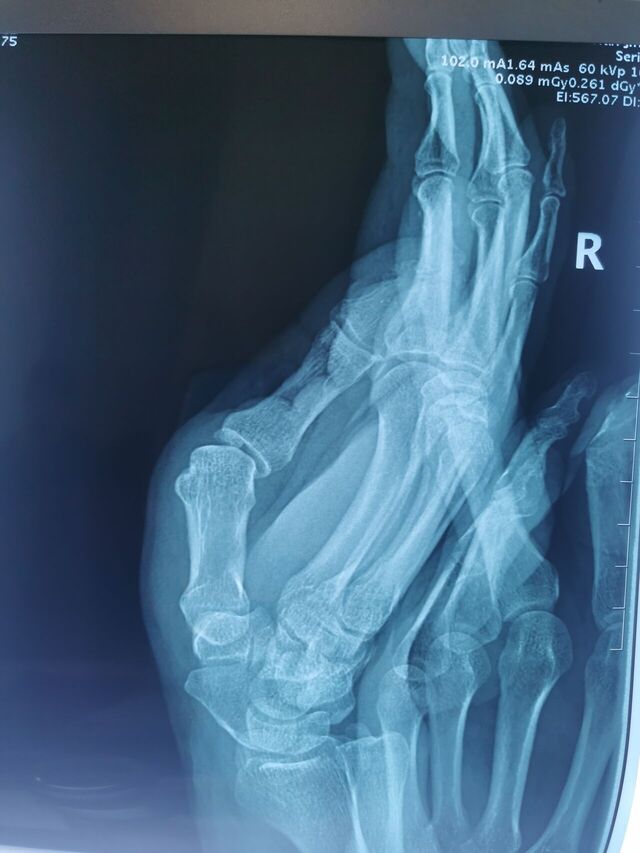

拇指掌指关节桡侧副韧带陈旧损伤

侧方应力试验(+)